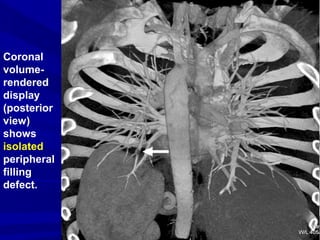

A diagnosis of PE is established

on the basis of individual

transverse sections, although,

extensive or

isolated PE,

as well as normal pulmonary

vasculature can be visualized by

means of 3D reconstructions.

Isolated

peripheral

pulmonary

embolus in

sixth-order

arterial

branch

shown as a

filling

defect.

Coronal

volume-

rendered

display

(posterior

view)

shows